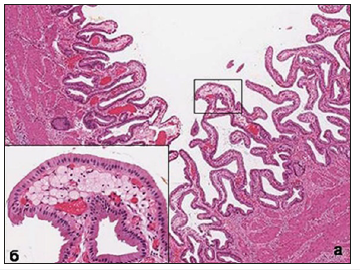

Since Virchov R, who first described this disease as early as 1857, the specific pattern of the internal surface of the gallbladder is the presence of multiple formations (inclusions) of various shades of yellow. The size of these formations and their appearance can vary greatly, but in most cases of diffuse cholesterosis, they have a width of 0.5-0.8mm, a length of 3-5mm or more, because they often merge together, forming a kind of mesh (mesh form) (Figure 1a). Comparing with the histological picture of the mucous membrane, it becomes clear that the yellowish formation on the surface is nothing other than the tops of the villi, in the apical part of which are accumulations of foam cells (Figure 1b) translucent through the single-layer epithelium. Back in 1923, Boyed [1] established that the contents of the cytoplasm of these cells are represented by cholesterol esters. Histological and electron microscopic examination of foam cells shows that, depending on the phase of life, the contents of the cell can vary and are structurally quite diverse.

Figure 1:(a) Macroscopic picture of the inner surface of the gallbladder with the classic mesh form of cholesterosis.

When studying the mucous membrane of the gallbladder in patients with cholesterosis, the main accumulations of foam cells are found in the tops of the villi. When foam cells completely fill the entire space of their own plate, forming the shape of a micropip, the stromal elements almost completely disappear. There is a compression of the capillary bed, which leads to ischemia of the surface epithelium of the mucous membrane and the deterioration of its metabolism. There is a decrease in the height of epithelial cells, the appearance of signs of a decrease in functional activity and, quite often. their desquamation. At the same time, in the neighboring areas of the same villus and in the adjacent villi, the accumulation of foam cells may be substantially less, or not observed at all. In other clinical cases, the spread of the process can go more intensively “and in breadth and depth.” Foam cells begin to accumulate intensively in the adjacent apical portions of the villi and in their deeper parts (as if in the neck of a micropolyp) (Figure 2), often reaching before fibromuscular layer. AT the final the result frothy cells of these compartments merge into one whole, forming large cholesterol polyp, visible without any microscope (Figure 3a).

Figure 3:(a) Cholesterol polyp with polypus mesh form of cholesterosis. Stained with hematoxylin and eosin. Increase x40.